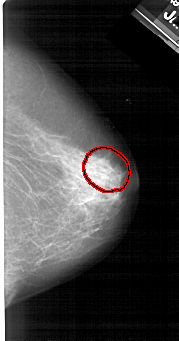

A_1378_1.RIGHT_MLO

RIGHT_MLO LINES 5281 PIXELS_PER_LINE 3151 BITS_PER_PIXEL 12 RESOLUTION 43.5 OVERLAY

FILE: A_1378_1.RIGHT_MLO.OVERLAY

TOTAL_ABNORMALITIES 1

ABNORMALITY 1

LESION_TYPE CALCIFICATION TYPE PLEOMORPHIC DISTRIBUTION SEGMENTAL

ASSESSMENT 4

SUBTLETY 2

PATHOLOGY BENIGN

TOTAL_OUTLINES 1

BOUNDARY